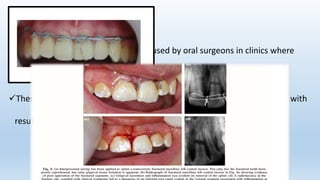

Wire ligature splints are sometimes used by oral surgeons in clinics where

dental splinting materials may not be available.

These splint types are generally rigid and impinge on the gingival tissues with

resulting inflammation.